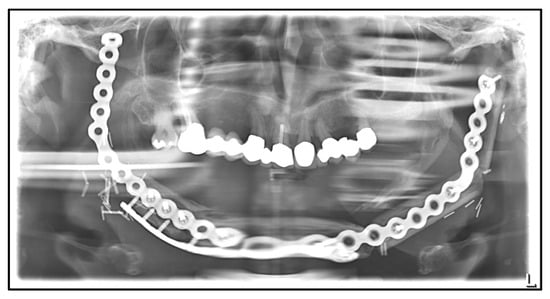

| Date | Intervention |

|---|---|

| 2000: | Initial diagnosis of prostate cancer with vertebral metastasis. Following radical prostatectomy with adjuvant radiotherapy and intravenous bisphosphonate therapy with zoledronate 4mg monthly and denosumab every 6 weeks. |

| July 2014: | Diagnosis of MRONJ in the right molar region of the mandible. Following mandibular box resection and protective plate osteosynthesis with a patient-specific plate. |

| August 2016: | Extraction of the second lower right premolar with smoothening of bony edges due to extraoral chronic fistula. |

| June 2017: | Removal of the reconstruction plate in the right mandible, re-osteosynthesis, and excision of a submandibular fistula on the right. |

| August 2018: | Partial mandibular resection with continuity defect and alloplastic reconstruction using a patient-specific plate, excision of a submental fistula |

| November 2018: | Cervical abscess on the right side with infected osteosynthesis material. Decortication and partial removal of the PSI. |

| December 2018: | Submental abscess on the left: extraoral abscess incision. |

| April 2019: | Cervical abscess in the right jaw angle with extraoral plate exposure and chronic-purulent fistula: extraoral abscess incision. |

| February 2022: | Paramandibular abscess on the left: intraoral abscess incision. |

| July 2022: | Submandibular abscess on the left: extraoral abscess incision. |

| September 2022: | Partial mandibular resection from the left mandibular angle to the right mandible, including the right temporomandibular joint, CAD/CAM-guided reconstruction with a bilateral free scapula flap with skin island, and patient-specific plate. In the course: